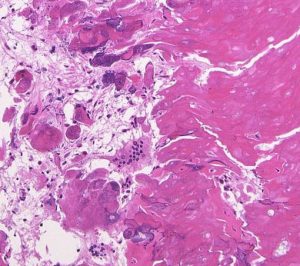

摘出した骨化片の病理像です。成熟した骨組織 mature boneです。

adamantinomatous typeです。mature boneの端には破骨巨細胞が多数見られます。

鞍内にあった部分の病理所見です。adamantinoomatous typeで,破骨細胞を伴う強い骨化がみられます。